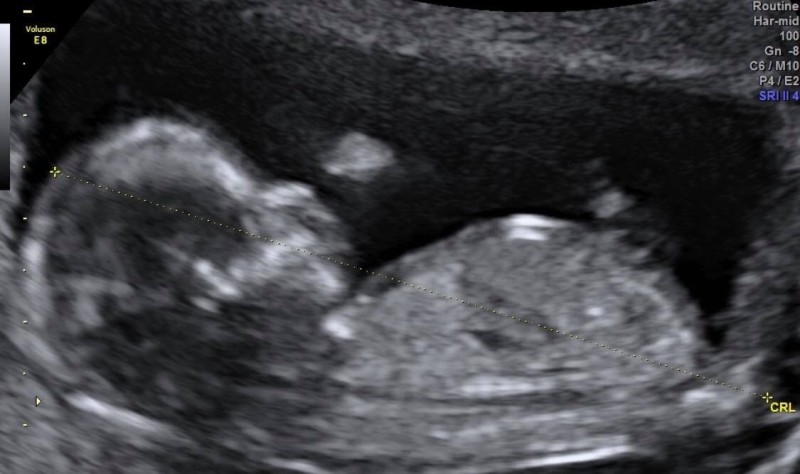

魏如萱谈到:“每一次妇科检查,医生都会告诉我比较难受孕,子宫的分数也是低于标准,我也有想过要不要先冻卵或是寻求其他方式,最后还是决定顺其自然就好,如果没有小孩也没关系,我身边还有很多可爱的小朋友,就算要认养也是可行的,虽然这样想,我心底仍抱持着期望和信心,我觉得一定可以!”

前阵子传言她怀孕,魏如萱却否认,原来也有所顾忌,她说:“之前一开始偶尔会出血的状况不是太稳定,有打针也有吃药,我的心情是很忐忑不安的,真的是花了一些时间才比较适应还有比较稳定,希望你们能体谅我到现在才分享这个消息。”